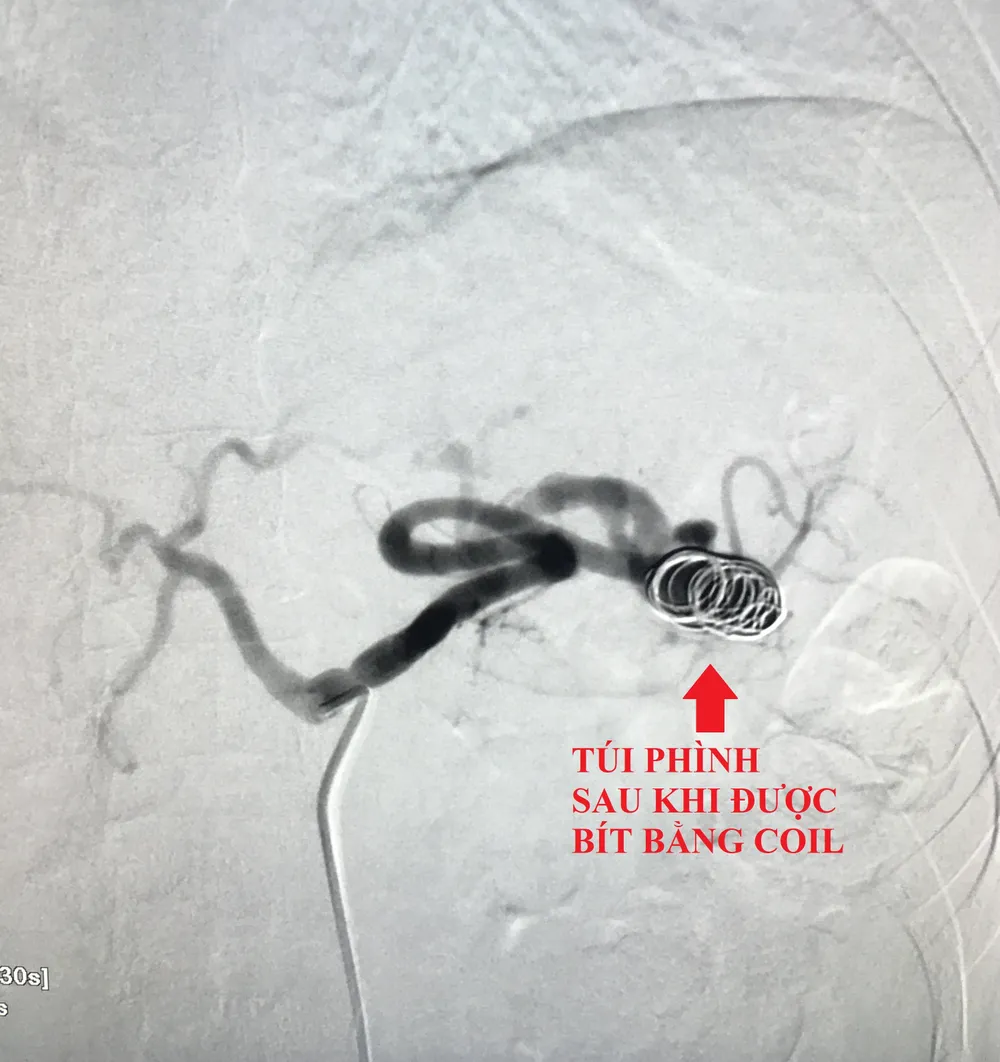

Bệnh nhân được lựa chọn can thiệp bằng ống thông với hỗ trợ của hệ thống chụp xóa nền mạch máu DSA qua đường mạch máu nhằm tránh nguy cơ phẫu thuật phải cắt lách.

Theo đó, các bác sĩ mở một lỗ nhỏ ở động mạch đùi, qua đó luồn ống thông vô đến lỗ động mạch lách, sau đó đến vị trí túi phình và thả 3 coil (vòng xoắn kim loại) bít hoàn toàn túi phình. Bệnh nhân hết đau tức vùng bụng và được xuất viện sau 2 ngày.

Túi phình động mạch lách sau khi được bít bằng coil. Ảnh: BVCC